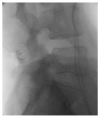

Osteoarthritis is a degenerative condition affecting the whole joint with the underlying bone, representing a major source of pain, disability, and socioeconomic cost worldwide. Age is considered the strongest risk factor, albeit abnormal biomechanics, morphology, congenital abnormality, deformity, malalignment, limb-length discrepancy, lifestyle, and injury may further increase the risk of the development and progression of osteoarthritis as well. Pain and loss of function are the main clinical features that lead to treatment. Although early manifestations of osteoarthritis are amenable to lifestyle modification, adequate pain management, and physical therapy, disease advancement frequently requires surgical treatment. The symptomatic progression of osteoarthritis with radiographical confirmation can be addressed either with arthroscopic interventions, (joint) preservation techniques, or bone fusion procedures, whereas (joint) replacement is preferentially reserved for severe and end-stage disease. The surgical treatment aims at alleviating pain and disability while restoring native biomechanics. Miscellaneous surgical techniques for addressing osteoarthritis exist. Advanced computer-integrated surgical concepts allow for patient personalization and optimization of surgical treatment. The scope of this article is to present an overview of the fundamentals of conventional surgical treatment options for osteoarthritis of the human skeleton, with emphasis on arthroscopy, preservation, arthrodesis, and replacement. Contemporary computer-assisted orthopaedic surgery concepts are further elucidated.